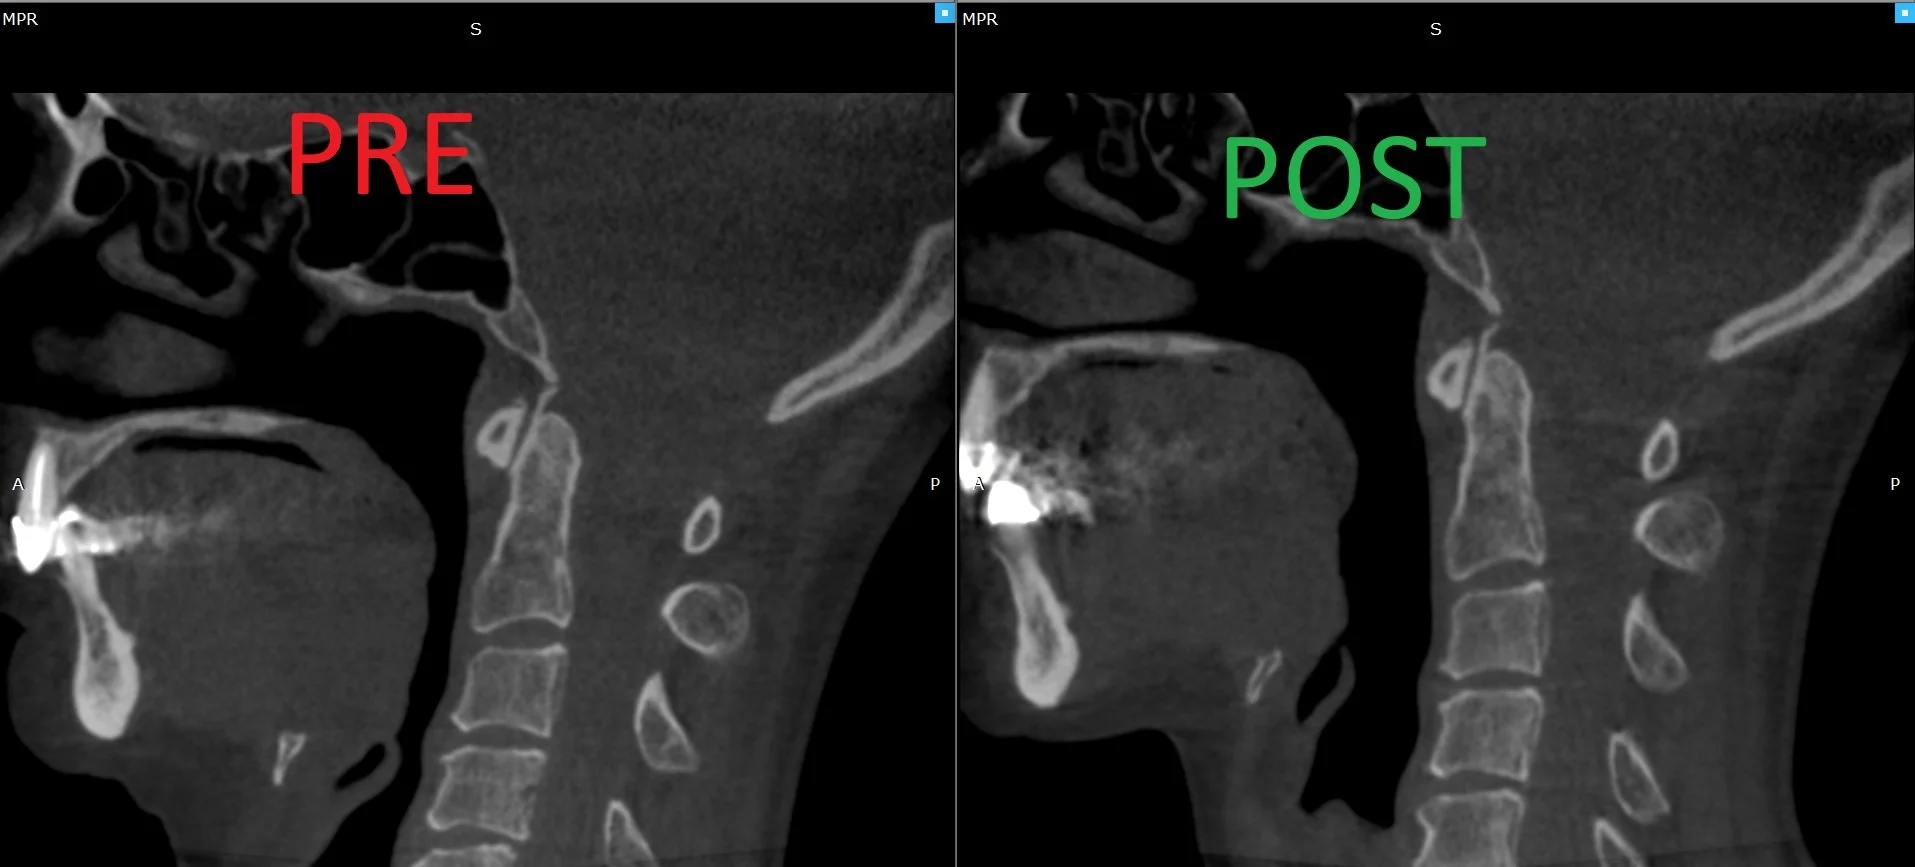

Our case studies highlight the transformative impact of Atlas Orthogonal chiropractic care. Each case features detailed pre- and post-treatment X-rays, showcasing precise corrections made to the upper cervical spine. Alongside these images, you'll find an overview of the patient’s initial symptoms—such as headaches, neck pain, vertigo, or postural issues—and the improvements they experienced after care. These cases provide an in-depth look at the science and results behind this specialized approach, demonstrating the effectiveness of gentle, non-invasive adjustments.

By exploring these case studies, you'll see the unique challenges our patients faced and how personalized Upper Cervical care helped restore their health and well-being. From reducing CCJ dysfunction to significant symptom relief, these stories emphasize the role of precise upper cervical care in achieving lasting results. Whether you're seeking answers for your own condition or simply curious about the process, these real-world examples illustrate how life-changing this specialized chiropractic technique can be.